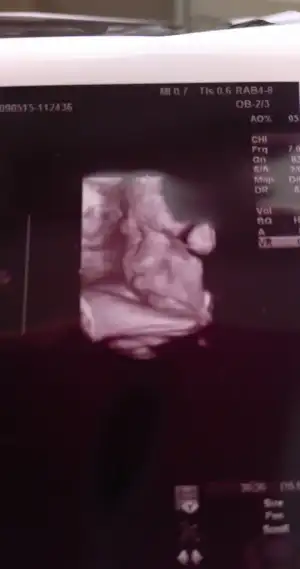

Günaydin annisler sonunda mutlu gün geldi, kızımı gördüm.

2805 gr olmuş ve doktor epey uzun boylu olacak dedi 51 cm mis boyu :)

nstye girdik ilk defa kızım oynamadi inat etti onun icin iki kere girdik,

Vee dogum tarihi olarak 31 mayis dedi :)

çook güzel bir kız bu dedi bi güzel sevdi de kızımı :))